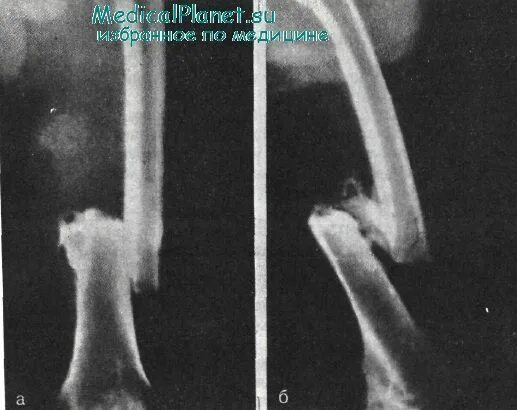

Неправильно срослась кость после перелома